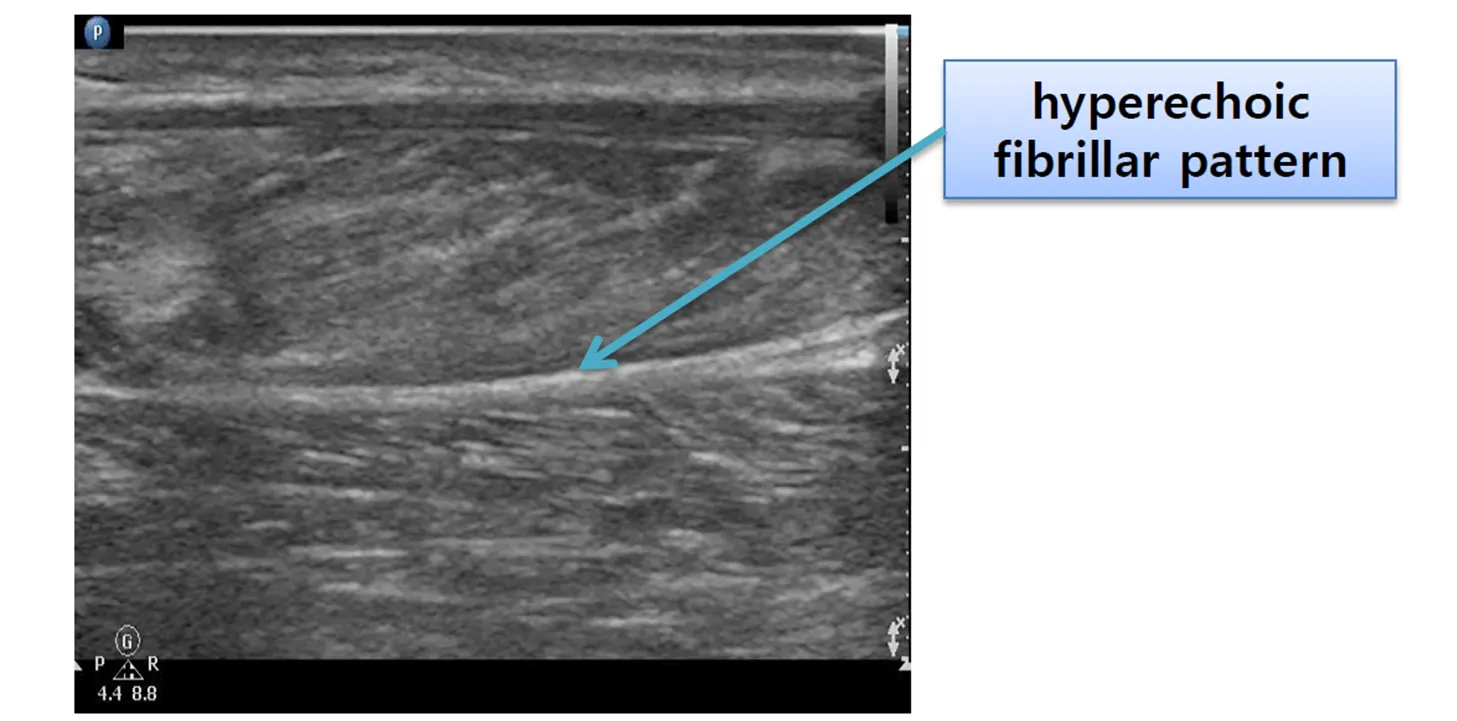

Fascia; 근육과 근육 사이에 hyperechoic fibrillar pattern으로 주행

Tendon; short axis에서 hyperechoic, longitudinal;fibrillar pattern

Bone 위에 올려져있는 tendon

Perpendicular하면 hyperechoic한 fibrillar pattern

Perpendicular 하지 않은건 hypoechoic

Tendon의 Hypoechoic: tendinopathy or trauma에 의한 tearing 등 병변 시사하므로 artifact인지 구분해야함; perpendicular하게. 2 axis로 잡아야함